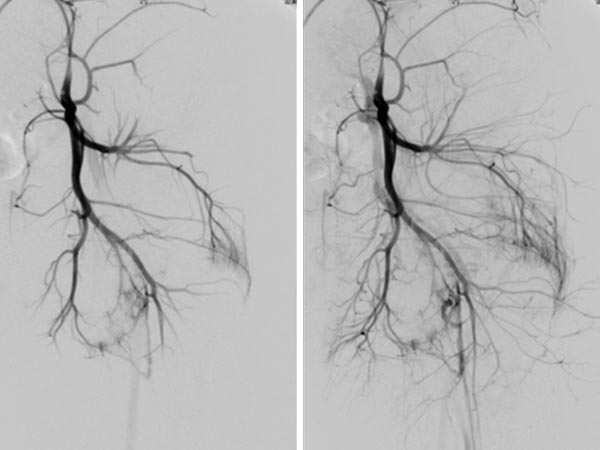

MIP-Rekonstruktion einer kontrastmittelunterstützen, dynamischen MR-Angiographie des Beckens und der Oberschenkel. Während auf der normalen rechten Seite hier noch eine arterielle Phase vorliegt, sind die Arterien und Venen der linken Seite massiv dilatiert und durch die multiplen arteriovenösen Fisteln des Parkes-Weber-Syndroms bereits die abführenden Venen kontrastiert.

In der DSA vor Embolisation (linkes Bild) finden sich kniegelenksnah multiple feine AVMs. Im Nativröntgenbild nach Embolisation ist das röntgendichte Embolisat zu sehen (mittleres Bild), das die arteriovenösen Fisteln ganz ausfüllt. In der DSA nach Embolisation (rechtes Bild) ist der gesamte Nidus der AVM verschlossen, keine sichtbaren arteriovenösen Fisteln mehr.